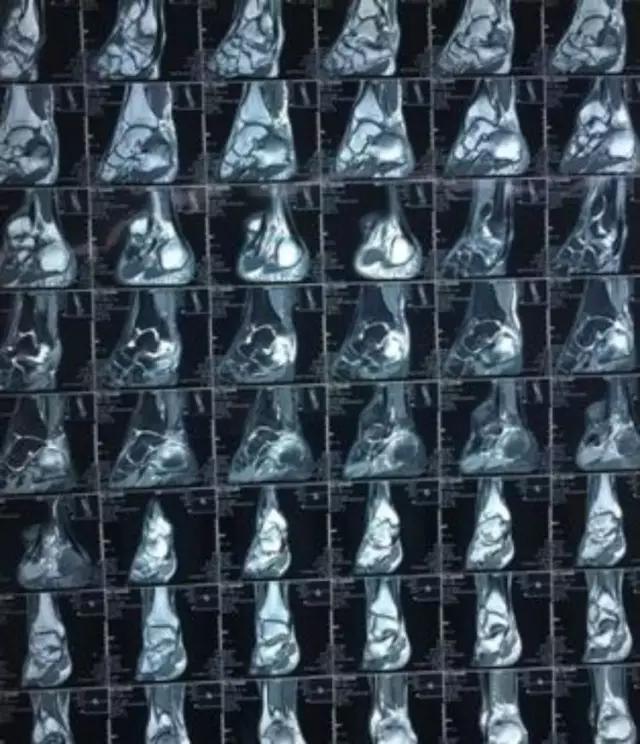

必须适应阅看不同质量的片子——

很多MRI的设备并不好,体位不好,片子质量差,甚至还经过手机翻拍,不管怎样,我们也要想尽办法抓住某些特征性的改变,大海中捞针,想尽办法得出诊断!